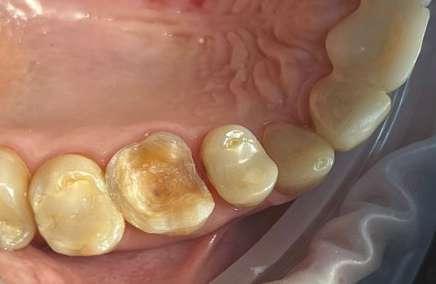

Se comienza el caso elaborando un enfilado dental a manera de maqueta para llevar a cabo la evaluación de la futura dimensión vertical planificada y con ello, el desgaste a realizar para que los órganos dentales reciban las coronas primarias que serán elaboradas en ZrO2 (Prettau® 2 Dispersive®, Zirkonzahn Worldwide). Las preparaciones de las coronas prima-

ras nos proporcionaban 1 mm de espacio protésico para poder otorgarles el grosor necesario y así evitar la posibilidad de algún daño biológico (Fig. 2a). Una vez realizadas las preparaciones, se procede a tomar impresión fisiológica con técnica de doble hilo a un tiempo, con material de polivinilsiloxano (Virtual, Ivoclar Vivadent) (Fig. 2b).

Se envía el modelo de trabajo articulado al laboratorio, se diseñan y elaboran las coronas primaras de ZrO2 con una angulación en sus paredes de 4 grados con el fin de obtener, no solo una buena retención, sino también una buena pasividad.

Las coronas secundarias que irán dentro de la prótesis removible fueron fabricadas con PEEK (Tecno Med, Zirkonzahn Worldwide) (Fig. 2d).

Se realizó la prueba de éstas intraoralmente para confirmar la pasividad y se observa, que no solo se logró una buena pasividad, sino también una excelente integración a los tejidos blandos (Fig. 3a y 3b).